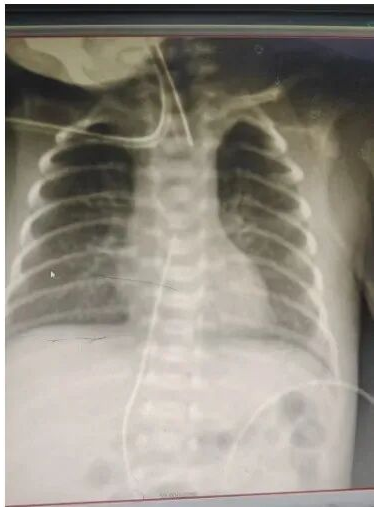

两名患儿均为极早早产儿:一名胎龄27+3周、出生体重1150克,一名胎龄26+周、出生体重960克。因胎龄极小、体重极低,全身器官发育极不成熟,血管纤细如发丝,外周静脉穿刺难度极大,快速建立安全、持久的静脉通路是抢救成功的关键。

在胥亚福副主任的全面统筹下,新年第一天为1150克早产宝宝成功实施脐静脉导管置入术(UVC)。该技术为阿坝州首例,能快速建立紧急生命通路,为超早产儿早期抢救、用药、营养支持赢得黄金时间,填补了我州在超早产儿、极低体重儿快速静脉通路救治领域的技术空白。

与此同时,在医疗团队精准评估下,儿科PICC护理团队迎难而上、精细操作,为960克超早产宝宝成功经外周静脉置入中心静脉导管(PICC),创下阿坝州最小体重早产儿PICC置管纪录。此项技术突破,实现了极低体重儿长期、安全、高渗透压营养输注与重症救治的管路保障,标志着我院新生儿重症护理技术再攀新高。